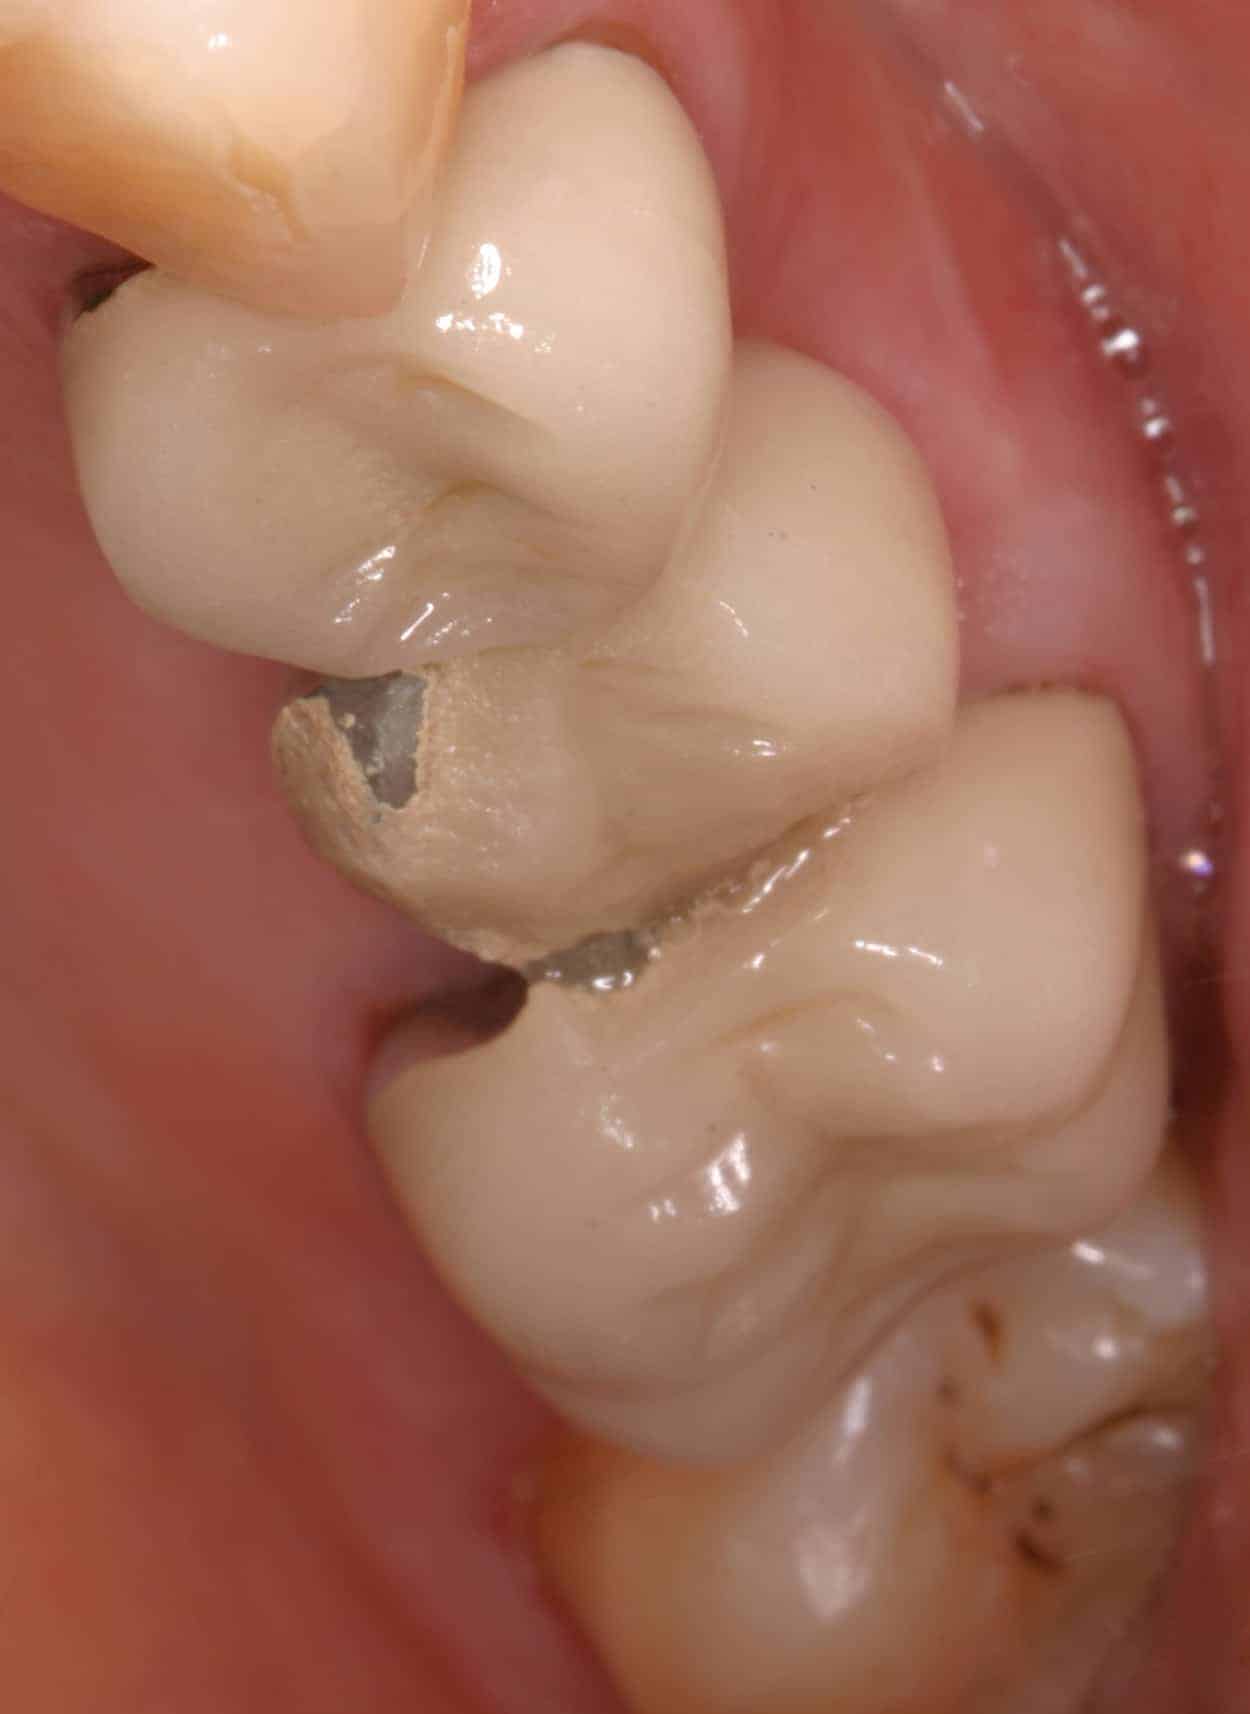

Before:Â Failed upper posterior three-unit bridge. Tooth #14 (upper left first molar) requires root canal therapy. Ideal candidate for a single dental implant to replace missing tooth #13 (upper left second premolar) and two single crowns on abutment/support teeth 12 (upper left first premolar) and 14. However, the patient is not interested in implant therapy and would like revision crown and bridge (fixed partial denture) therapy.